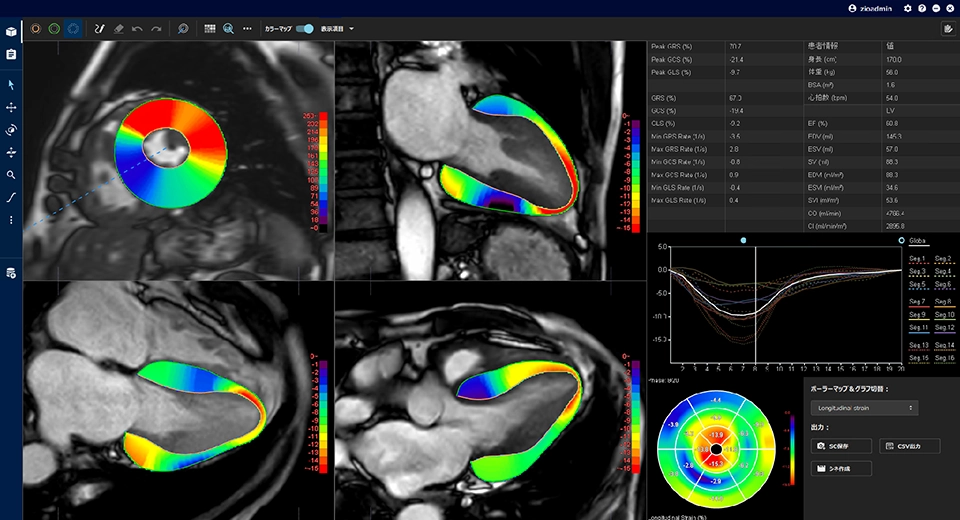

MRI検査 | きたがわ脳神経外科 | 北九州市八幡西区本城学研台の。APERTO Inspireと“癒し”を与える独自のシステムで快適なMRI検査。検査機材について|動物検診センター キャミック | 動物検診。検査機材について|動物検診センター キャミック | 動物検診。緑と黒のドレスを着た女性のポートレート